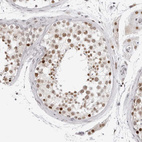

Immunohistochemical staining of human fallopian tube, liver, lymph node and testis using Anti-MSH6 antibody HPA028446 (A) shows similar protein distribution across tissues to independent antibody HPA028376 (B).